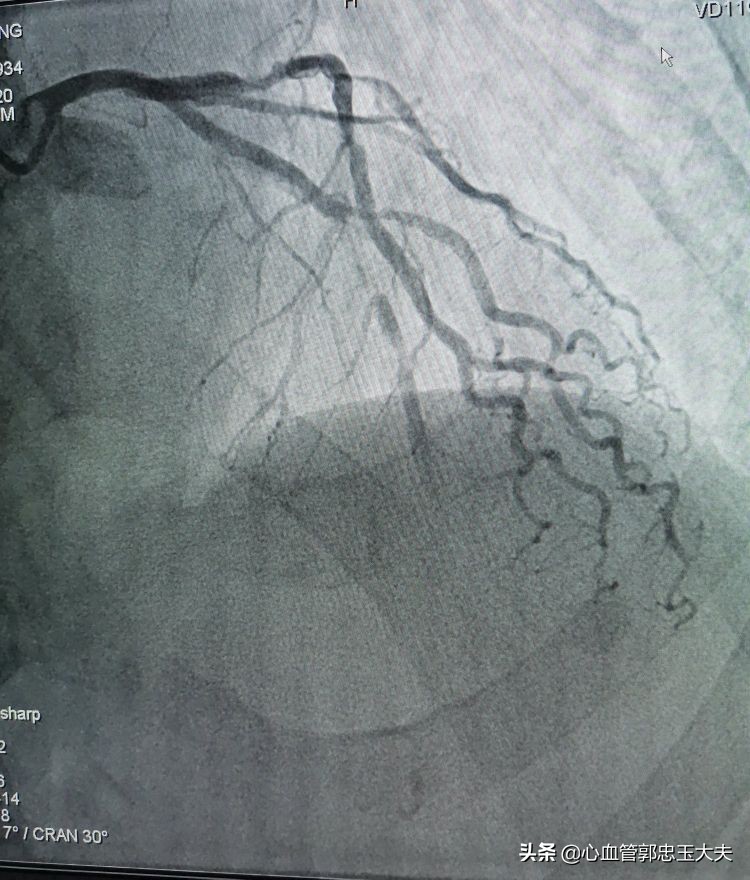

张大爷86岁了,有高血压病史,无烟酒嗜好。因为“反复胸闷头晕数月”入院。冠状动脉CTA示:三支病变,严重钙化合并高度狭窄。行冠脉造影示:前降支中远段钙化,完全闭塞,远端可见血管影。未见明显侧枝循环。(如下图)